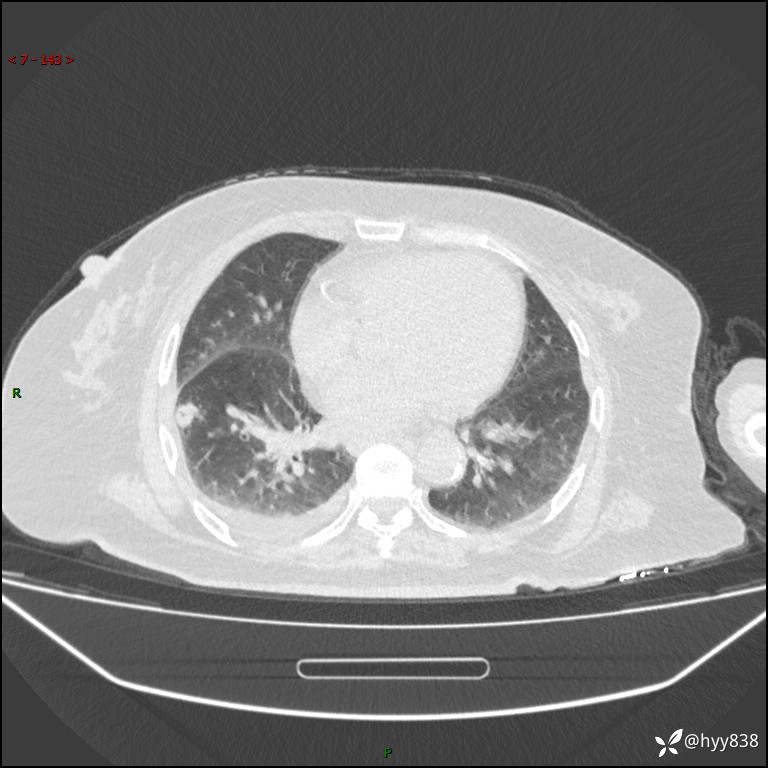

胸部 CT平扫、